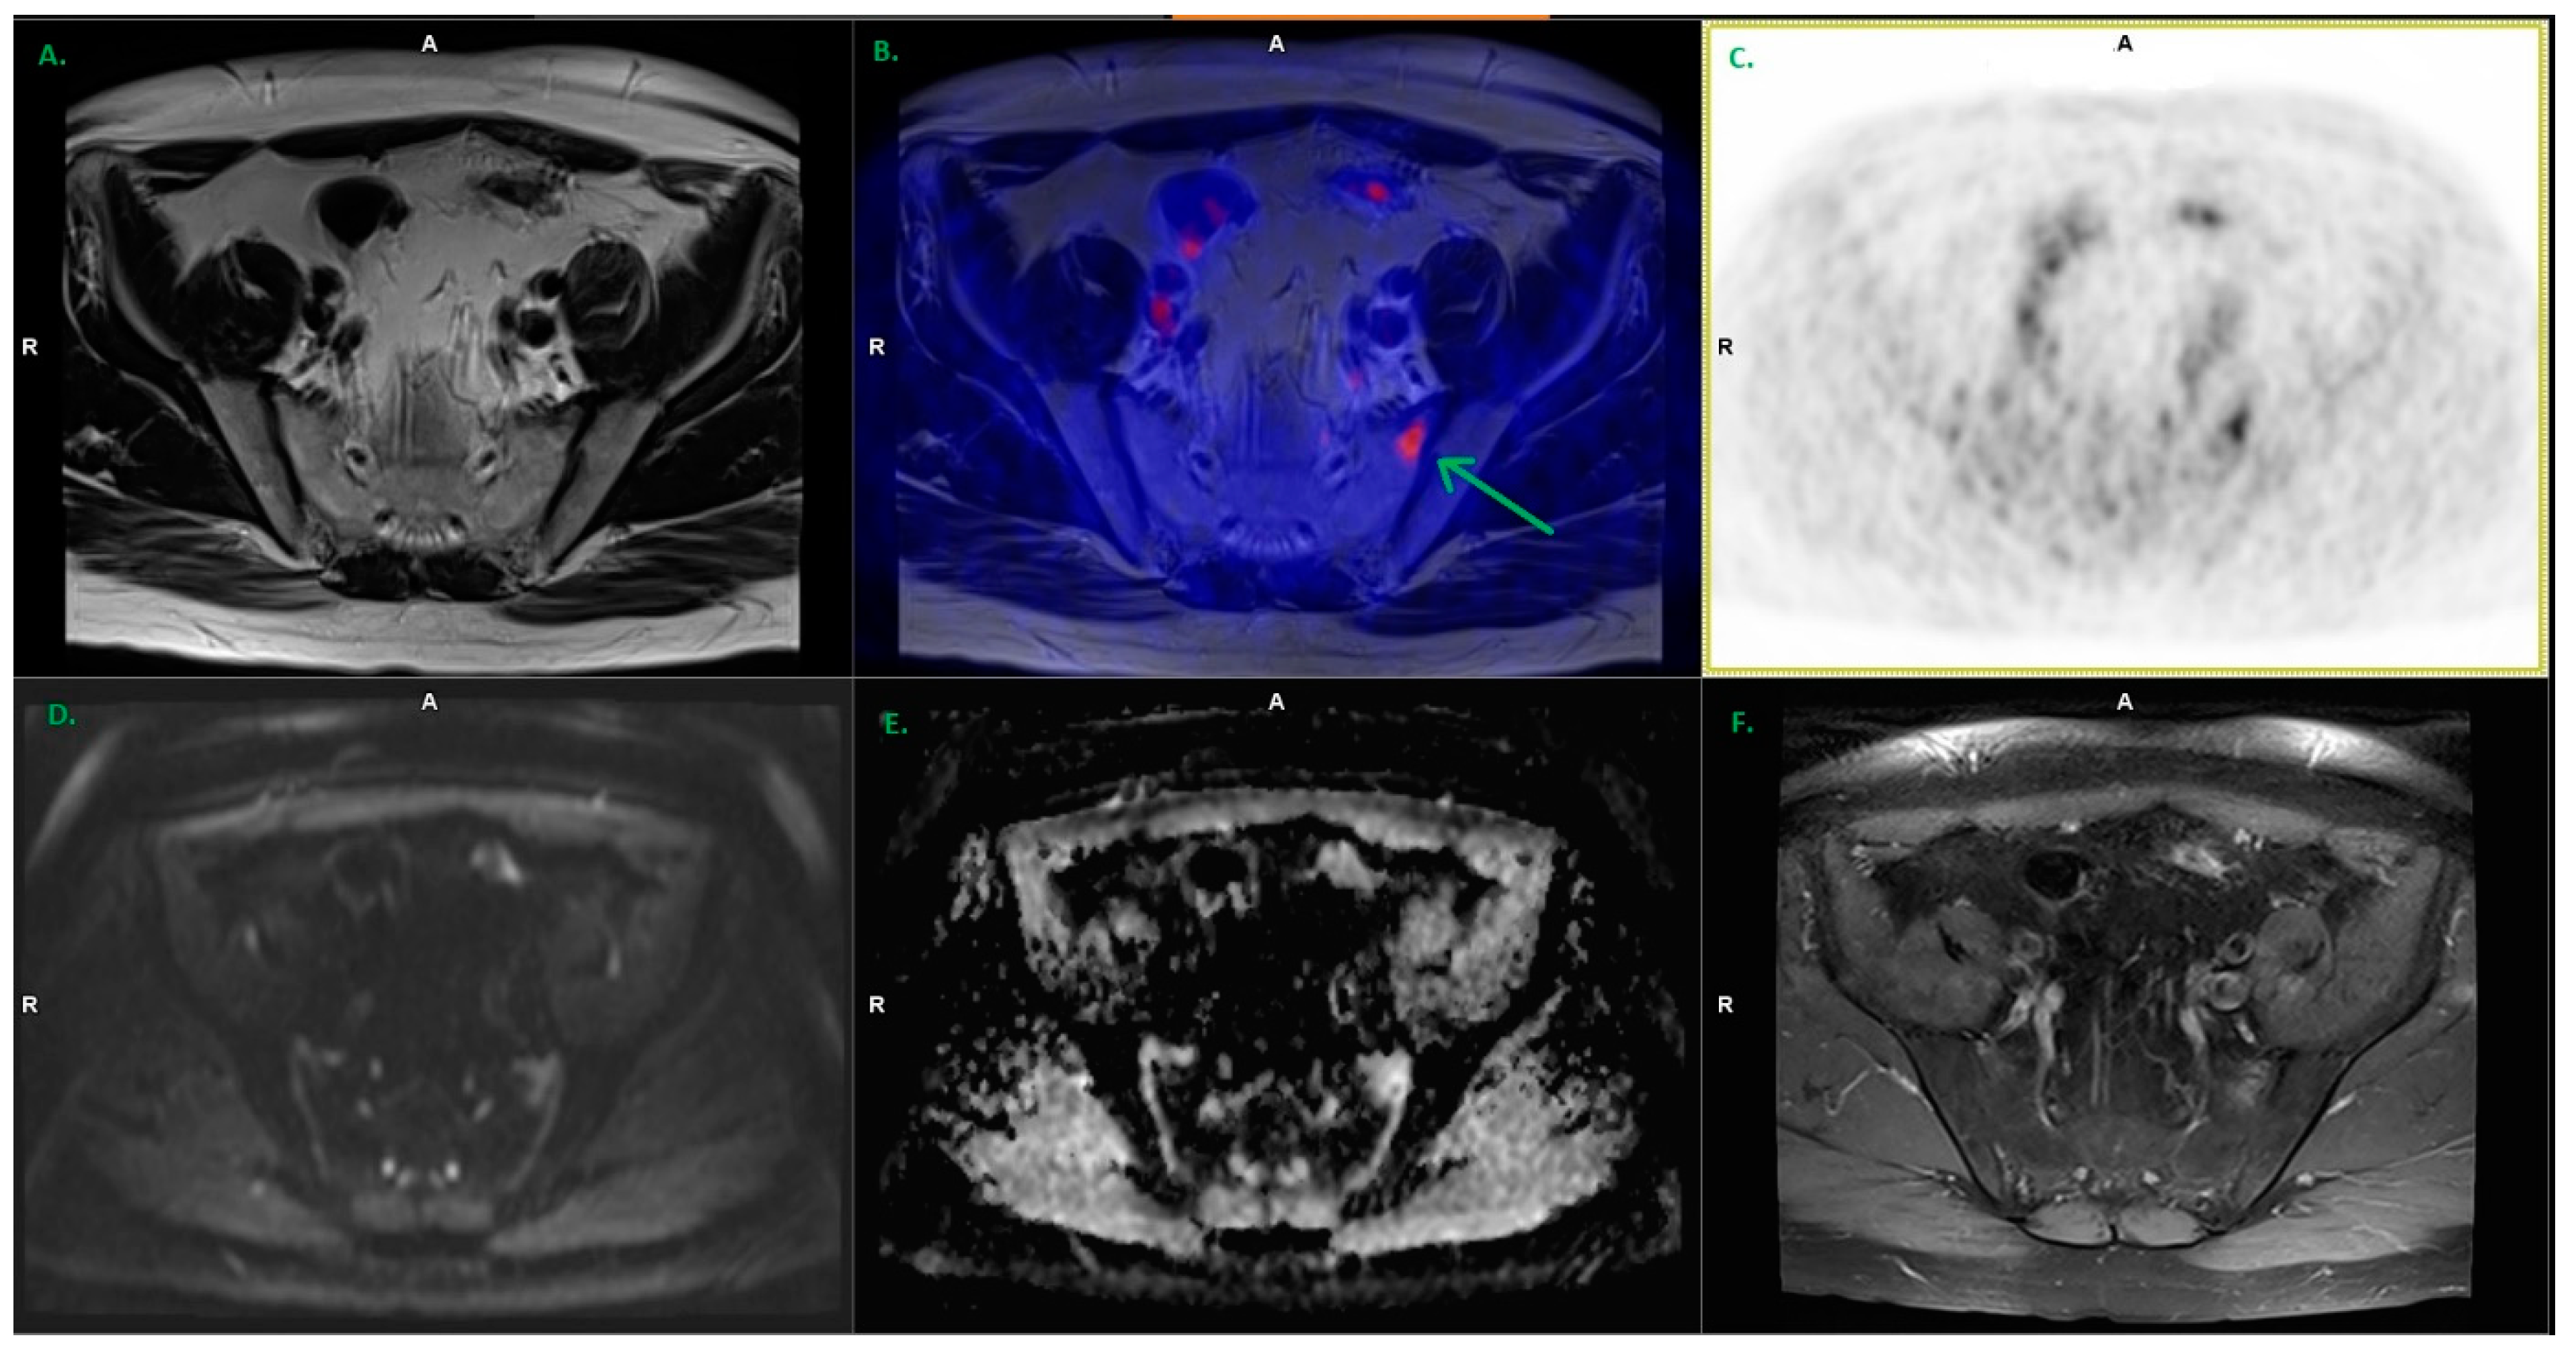

3.1. Local Recurrence

3.2. Lymph Nodes

| Recurrence Site | No. of Detected Lesions | Mean SUVmax ± SD | Size Range (mm) |

|---|---|---|---|

| Prostatic bed | 13 | 6.34 ± 2.53 | 6 × 4 up to 19 × 18 × 25 |

| Pelvic lymph nodes | 34 | 5.46 ± 3.28 | 3 × 3 up to 11 × 11 |

| Extrapelvic lymph nodes | 1 * | 3.75 | 3 × 3 |

| Bones | 5 | 4.75 ± 1.82 | 5 × 4 up to 8 × 8 |